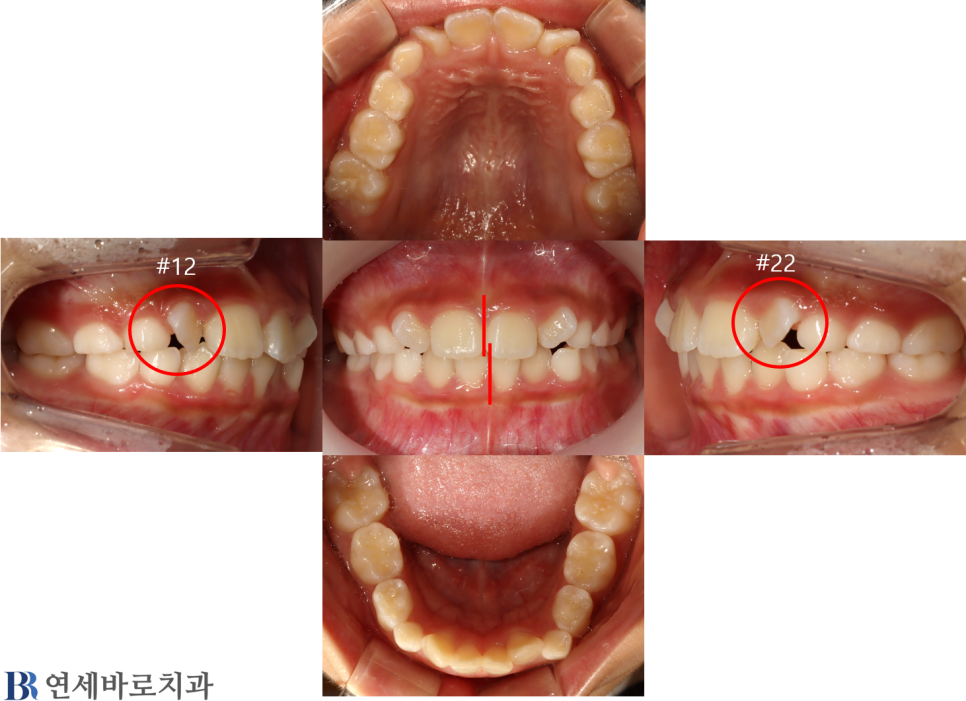

소아 교정 치료 #6

작성자

최고관리자

조회

639

작성일

24-01-12